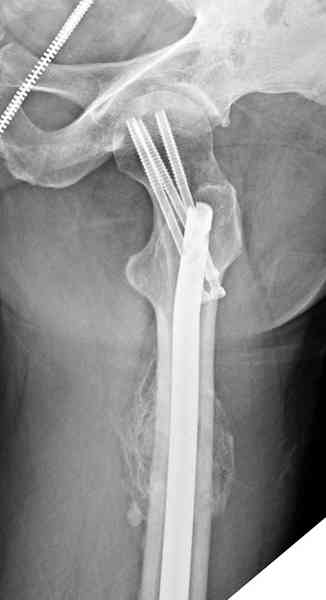

В первый же день произведено антеградное штифтованием DePuy Trochanteric Nail.

На второй день (7) обнаружен пропущенный перелом,

и проведены шурурпы через и спереди штифта без удаления.

Послеоперационные снимки